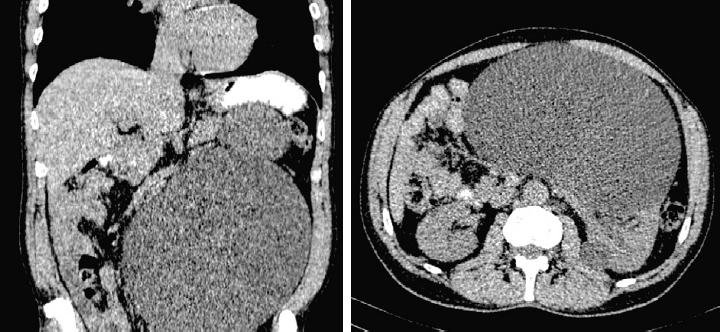

Пациент, 55 лет, был госпитализирован в хирургическое отделение СПбГБУЗ «Городская больница № 15» с жалобами на периодическую боль в животе, увеличение живота в размерах, невозможность похудеть при соблюдении диеты. Из анамнеза известно, что около года назад перенес двустороннюю пневмонию, в связи с чем за неделю до госпитализации выполнил контрольное КТ органов грудной клетки, где на краевых срезах диагностирована киста брюшной полости. Консультирован хирургом поликлиники, выдано направление для госпитализации. Пациенту в стационаре выполнена КТ органов брюшной полости с внутривенным контрастированием: в забрюшинном пространстве слева выявлены два образования жидкостной плотности, неправильно-округлой и округлой формы, четко очерченные, размерами до 224 × 140 × 240 и 84 × 79 × 78 мм соответственно (третий размер по сагиттальным срезам), без признаков накопления контрастного вещества на постконтрастных изображениях. Почки расположены в типичном месте, паренхима не истончена, однородной консистенции. Чашечно-лоханочная система левой почки расширена. Мочеточники с обеих сторон не расширены. Выделительная функция обеих почек своевременная, симметричная. Рентгеноконтрастных конкрементов в проекции мочевыводящих путей не выявлено. По результатам КТ сложилось впечатление, что оба кистозных образования исходят из левой почки. Установлен диагноз: «Кисты левой почки, тип II по классификации Bosniak» (рис. 1).

Рис. 1. Компьютерная томография органов брюшной полости с внутривенным контрастированием до операции.